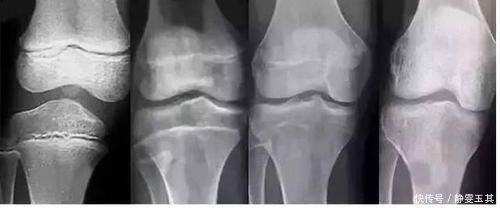

第二天,西西的母亲带着孩子去医院检查,西西虽然现在个子不矮,但是骨龄已经超前发育了,孩子的股侯倩可能会提前闭合,长不了很高了。